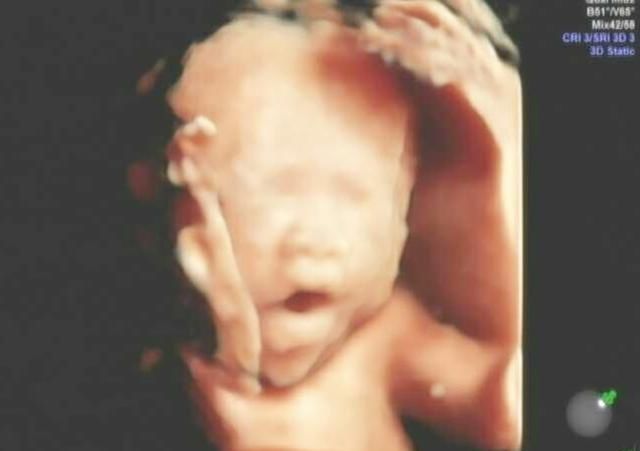

四维检查一般是在24周左右,主要检查的是孩子的发育问题,是否有畸形和先天的疾病,会详细检查大脑、脊柱和四肢的发育情况。

只要没有这些情况都是正常的,从怀孕周数上来看,属于孕中期,距离40周出生还需要一段时间继续发育,所以看起来会有点丑。

妈妈在肚子里活动的空间比较小,还会因为活动的原因对身体造成挤压,当妈妈做四维检查的时候,可能孩子正被挤到脸部,所以会看起来皱巴巴的好像很丑的样子。

四维检查是通过声波的反馈给出的图形显示,并不是真的透过妈妈的肚子看到了孩子的样貌。四维的检查是需要不断移动仪器来判断的,这个过程不排除羊水、脐带等会对反馈的图片造成干扰,导致孩子的样貌形成有偏差。

虽然很多人看到出生的孩子和四维很像,但仔细分辨看还是有很大差别的。即便是成人通过四维扫描拍出来的照片也不会太好看,何况是小婴儿。